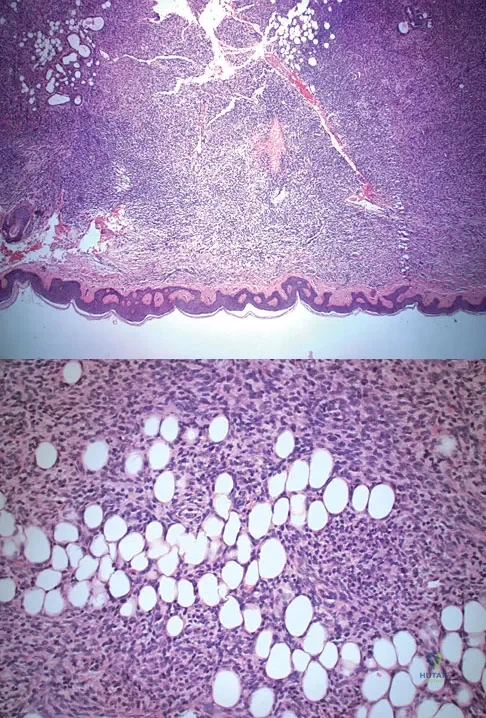

A 10-year-boy has had thigh pain for the past several months. He denies any history of trauma. Examination reveals no soft-tissue mass, and mild tenderness. Figures 33a and 33b show the plain radiograph and MRI scan, and the biopsy specimens are shown in Figures 33c and 33d. What is the most likely diagnosis?

The diagnosis is eosinophilic granuloma. The plain radiograph and MRI scan show a lesion in the midshaft of the femur. There is no soft-tissue mass. There is reactive bone about the lesion that suggests a less aggressive tumor. The histology reveals eosinophils in an otherwise bland cellular background with no evidence of mitotic figures or malignant cells to suggest sarcoma. The diagnostic elements are the amphophilic (ie, pale purple) histiocytes with cigar-shaped nuclei, some of which have linear longitudinal grooves. There is no histologic evidence of infection. Lymphoma of bone would be an unusual occurrence in this age group, and the histology is not consistent with that diagnosis.